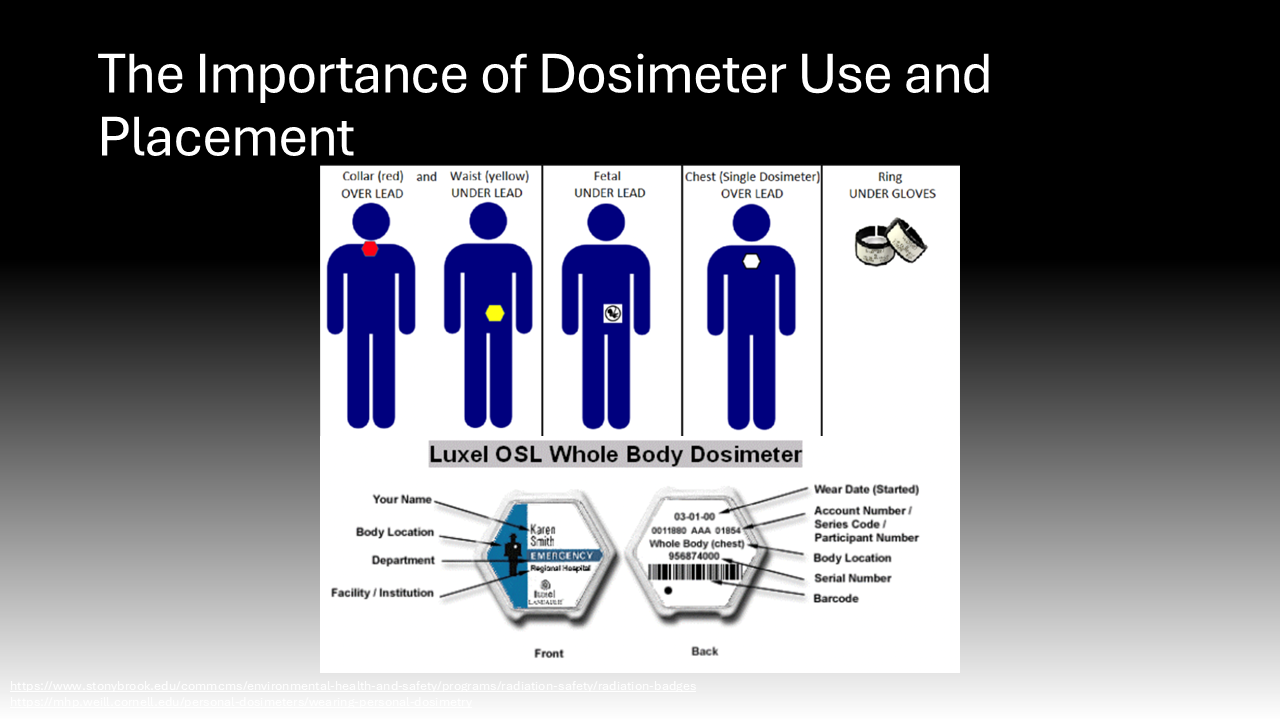

In the operating room, the core tenet of risk mitigation from intraoperative radiation exposure is known as “ALARA,” as low as reasonably achievable.6 This means surgeons are encouraged to use the lowest amount of radiation to achieve a safe surgical environment and outcome.6 To achieve ALARA, it is essential that surgeons wear dosimeters while in the OR to quantify their radiation exposure so it can be tracked by hospital occupational safety experts.15 Understanding their exposure is essential to alert them to their increased risk so they can accordingly mitigate radiation exposure. Many organizations and institutions set dose limits for radiation exposure for their physicians. For instance, the Cleaveland Clinic, a leader in the medical field sets the following annual limits of radiation exposure for their physicians: a maximal total effective/body dose (0.5 Sv), deep or organ dose (0.5 Sv), shallow/whole body skin dose (0.5 Sv), eye exposure (0.15 Sv), and special recommendations for pregnant women (0.005 Sv during pregnancy) and employees under 18 years of age (0.005 Sv).6